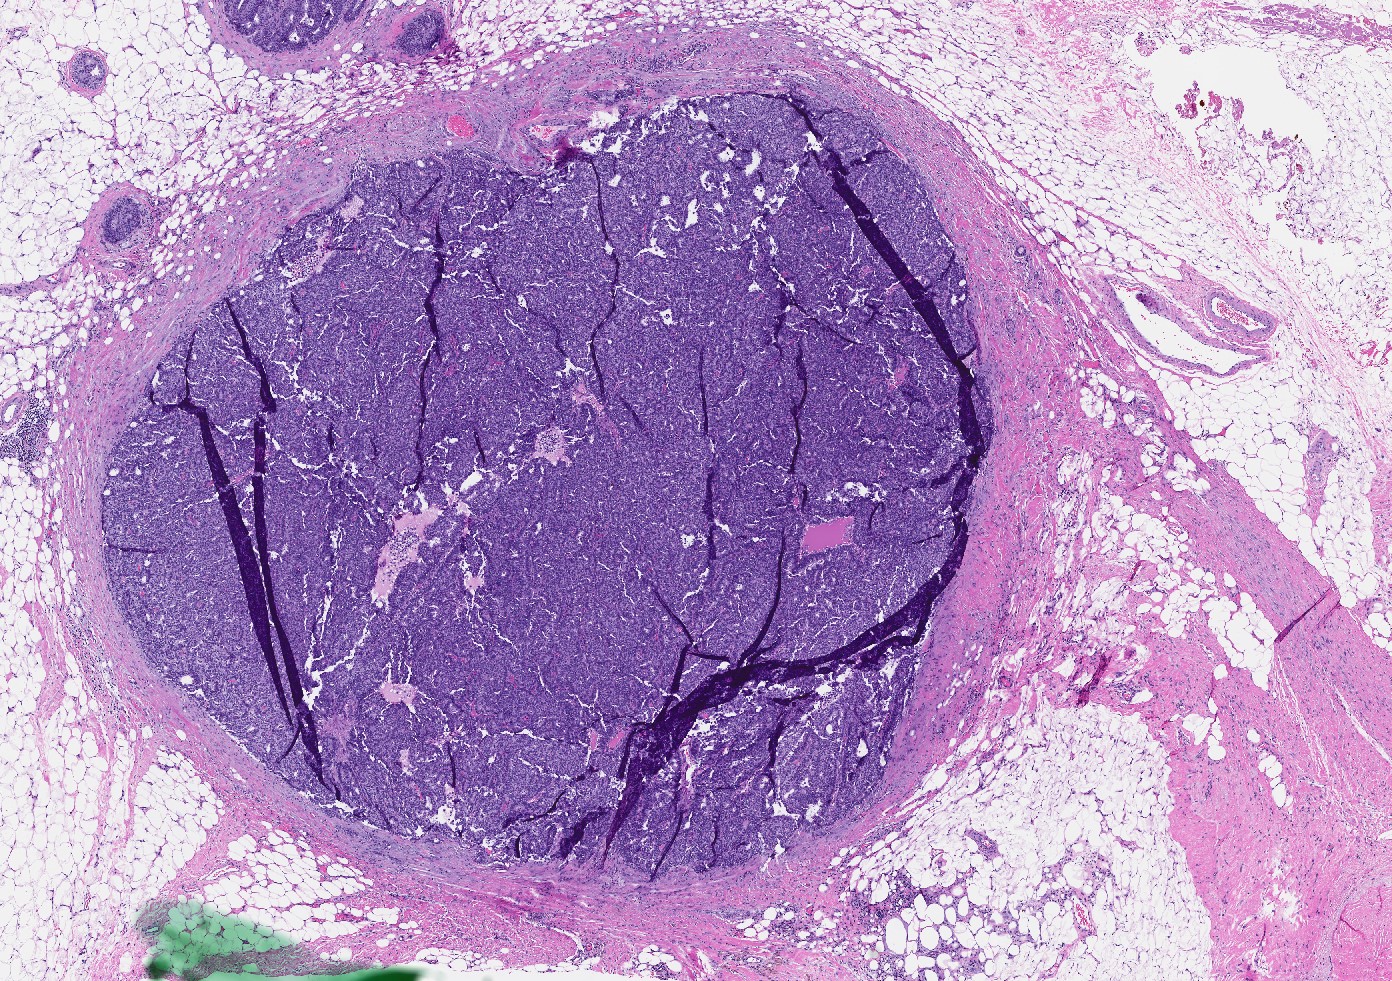

- Papillary tumor with pushing borders, may be within a cystically dilated duct, surrounded by a thick fibrous capsule (Histopathology 2008;52:20, Mod Pathol 2021;34:1044, Virchows Arch 2022;480:5)

- Delicate papillary fronds with fibrovascular cores lined by cuboidal to columnar epithelial cells with low to intermediate grade atypia

- Cribriform and solid architecture may be present

- Low mitotic activity (average 3 mitoses per 10 high power fields [HPFs]) (Am J Surg Pathol 2011;35:1)

- Most show complete lack of myoepithelial cells along the papillae and around the periphery of the tumor (Am J Surg Pathol 2006;30:1002, Am J Surg Pathol 2011;35:1)

- Basement membrane markers (collagen IV, laminin) may be expressed around the periphery (Pathobiology 2021;88:359, Am J Clin Pathol 2009;131:228)

- Invasive carcinoma is defined as the presence of neoplastic cells infiltrating beyond fibrous capsule (Mod Pathol 2021;34:1044)

- Most commonly invasive carcinoma of no special type (IDC NST), small (pT1), ER+, HER2- and low grade (Am J Surg Pathol 2011;35:1093, Breast J 2021;27:209, Breast J 2019;25:539, Curr Probl Cancer 2018;42:291)

- Staging is based on the size of the conventional invasive component if present

- Epithelial displacement / entrapment of neoplastic cells within capsule can occur and must be distinguished from true invasion beyond the fibrous capsule

Microscopic (histologic) images

Contributed by Kristen E. Muller, D.O. , Mariel Molina Nunez, M.D. and Julie Jorns, M.D. (Case #518)